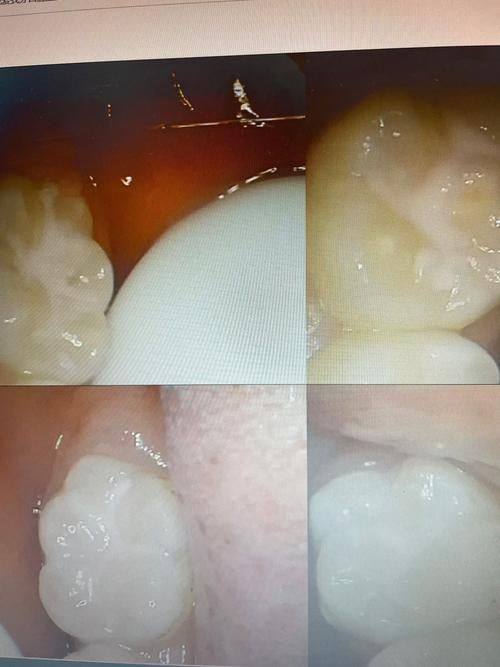

3. 根管治疗和牙齿修复:在这方面有独到之处,医生能够精细处理各种复杂的牙科问题,保护治疗成效。